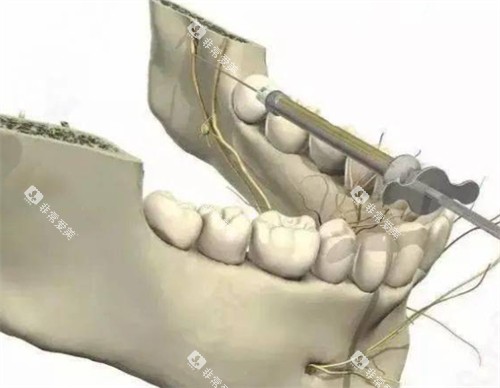

根管治疗主要用于治疗牙髓炎、根尖周炎等疾病。

张家口市第一医院口腔科的根管治疗收费与牙齿的位置和根管数量有关。

牙齿位置

前牙的根管治疗相对简单,一般一个根管的治疗费用在300 - 600元。

前磨牙有1 - 2个根管,治疗费用在500 - 1000元。

磨牙的根管数量较多,一般有3 - 4个根管,治疗费用在800 - 1500元。

根管复杂程度

如果根管存在钙化、弯曲等复杂情况,治疗难度增加,费用也会相应提高,可能会比正常情况多收200 - 500元。